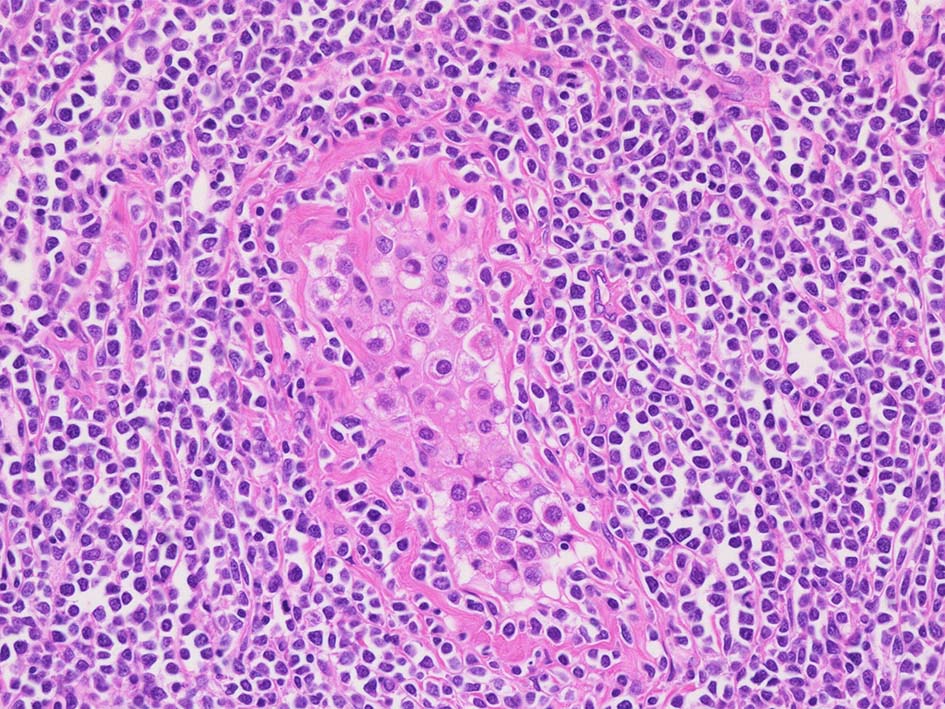

精細管の多くがスペアされ, 間質にlymphoid cellsが密に浸潤している. わずかな精細管に浸潤が認められ萎縮や破壊像が認められる. 精細管において Lymphoepithelial lesion(LEL)に似た所見がある.

類円形/多稜形の核をもつN/C比大の細胞. 粗大なクロマチンが増加, 核小体は不明瞭. DLBCLに認められるcentroblasts/ immunoblastsの細胞所見と異なる.